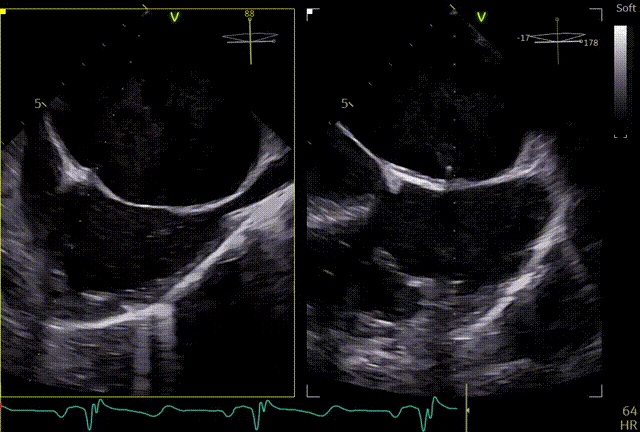

术前TEE评估

术前心超团队王蓓教授以及余婵教授对患者的瓣膜解剖情况进行了详细的评估:

① 二尖瓣后叶广泛栓系,前后叶对合不良,二尖瓣重度关闭不全,Carpentier分型Ⅲb,反流程度4+;

② 画迹法显示二尖瓣瓣口面积5.25cm²,平均跨瓣压差4.2mmHg;

③ 二尖瓣前叶(A1)长度28.5mm,二尖瓣后叶(P1)长度: 10.4mm;二尖瓣前叶(A2)长度28.4mm,二尖瓣后叶(P2)长度: 12.7mm二尖瓣前叶(A3)长度22.6mm,二尖瓣后叶(P3)长度: 11.5mm;

④ 3区前后叶对合gap 4.5mm,2区前后叶对合gap 3mm。

术前TTE

两腔心

短轴

四腔心zoom模式

反流情况